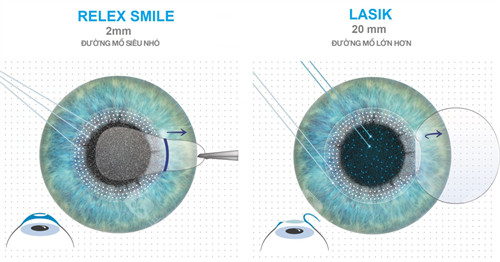

1、准激光手术(LASIK)

3、全飞秒SMILE手术

优势:无瓣小创口,适合运动员等特殊职业人群